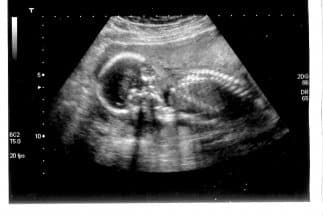

Controversia por propuesta de ley en Arizona que obliga a los doctores a informarles a sus pacientes de medicamentos que podrían revertir el aborto.

Esta medida obligaría a los doctores a informarles a sus pacientes de medicamentos que potencialmente podrían revertir los efectos de un aborto si se toman a tiempo.